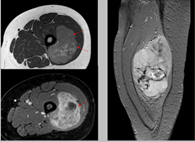

Pruebas de imágen

Las pruebas de diagnóstico por imágenes utilizan ondas sonoras, rayos X, campos magnéticos o sustancias radiactivas para crear imágenes del interior del cuerpo. Las pruebas de diagnóstico por imágenes pueden realizarse por diversos motivos, como:

Las imágenes más representativas o más comunes son:

3. Tomografía Computarizada

5. Resonancia Magnética